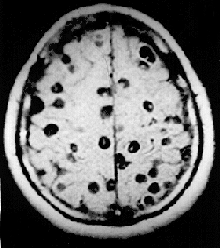

É diagnosticada por meio da Ressonância Magnética e da Tomografia Axial Computadorizada, os quais são de alta confiabilidade, permitindo saber a etiologia e definir o número, localização e extensão das lesões. Também se faz o diagnóstico através do estudo citológico e bioquímico do Líquido Cefaloraquideo (LCR)